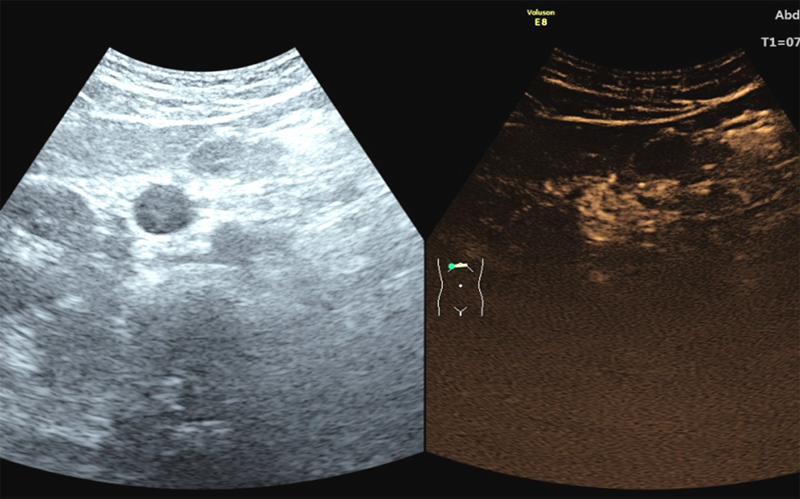

В Пироговском Центре внедрена и успешно применяется методика УЗ-исследования с контрастным усилением, что выводит диагностику паренхиматозных и сосудистых заболеваний на новый качественный уровень.

С 2015 года в Пироговском Центре проводится системная работа по применению ультразвукового контрастного препарата в лечебных целях (потенциировании эффекта) при выполнении УЗ-абляции образований печени, поджелудочной железы, миомы матки. С 2018 года УЗ-исследование с контрастным усилением применяется и в диагностических целях при выполнении УЗ-исследований органов и сосудов брюшной полости, забрюшинного пространства, молочной, щитовидной желез, мягких тканей. Метод позволяет не только выявить образования, но и провести дифференциальную диагностику между доброкачественными и злокачественными поражениями, оценить проходимость магистральных артерий и вен органов брюшной полости, выполнить УЗ-холангиографию, гистеросальпингографию.

Показания к применению УЗИ с контрастированием: очаговые поражения печени, поджелудочной железы, селезенки, почек (кисты, солидные образования, инфекционные болезни), патология брюшного отдела аорты, воротной вены.